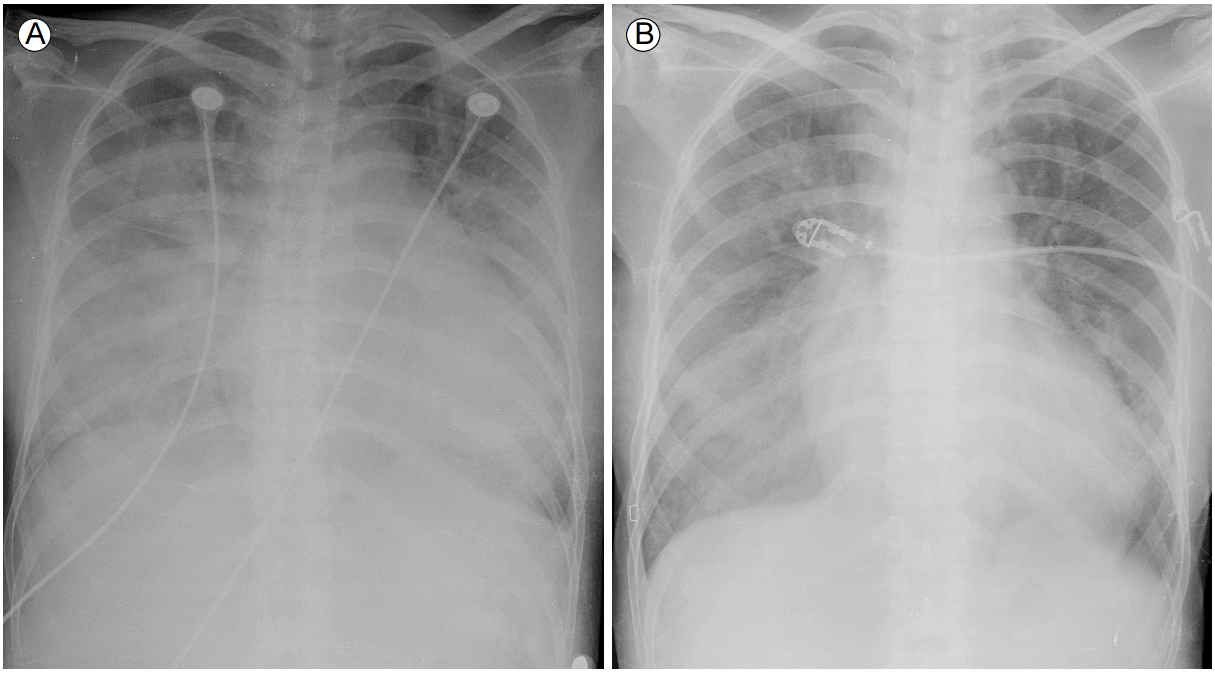

Figure 1.

(A) On admission, a chest x-ray revealed cardiomegaly, pleural effusion, and diffuse consolidation in both lung fields, which was dominant on the right side. (B) Following high dose steroid therapy, the extent and density of patchy air space consolidation was decreased.